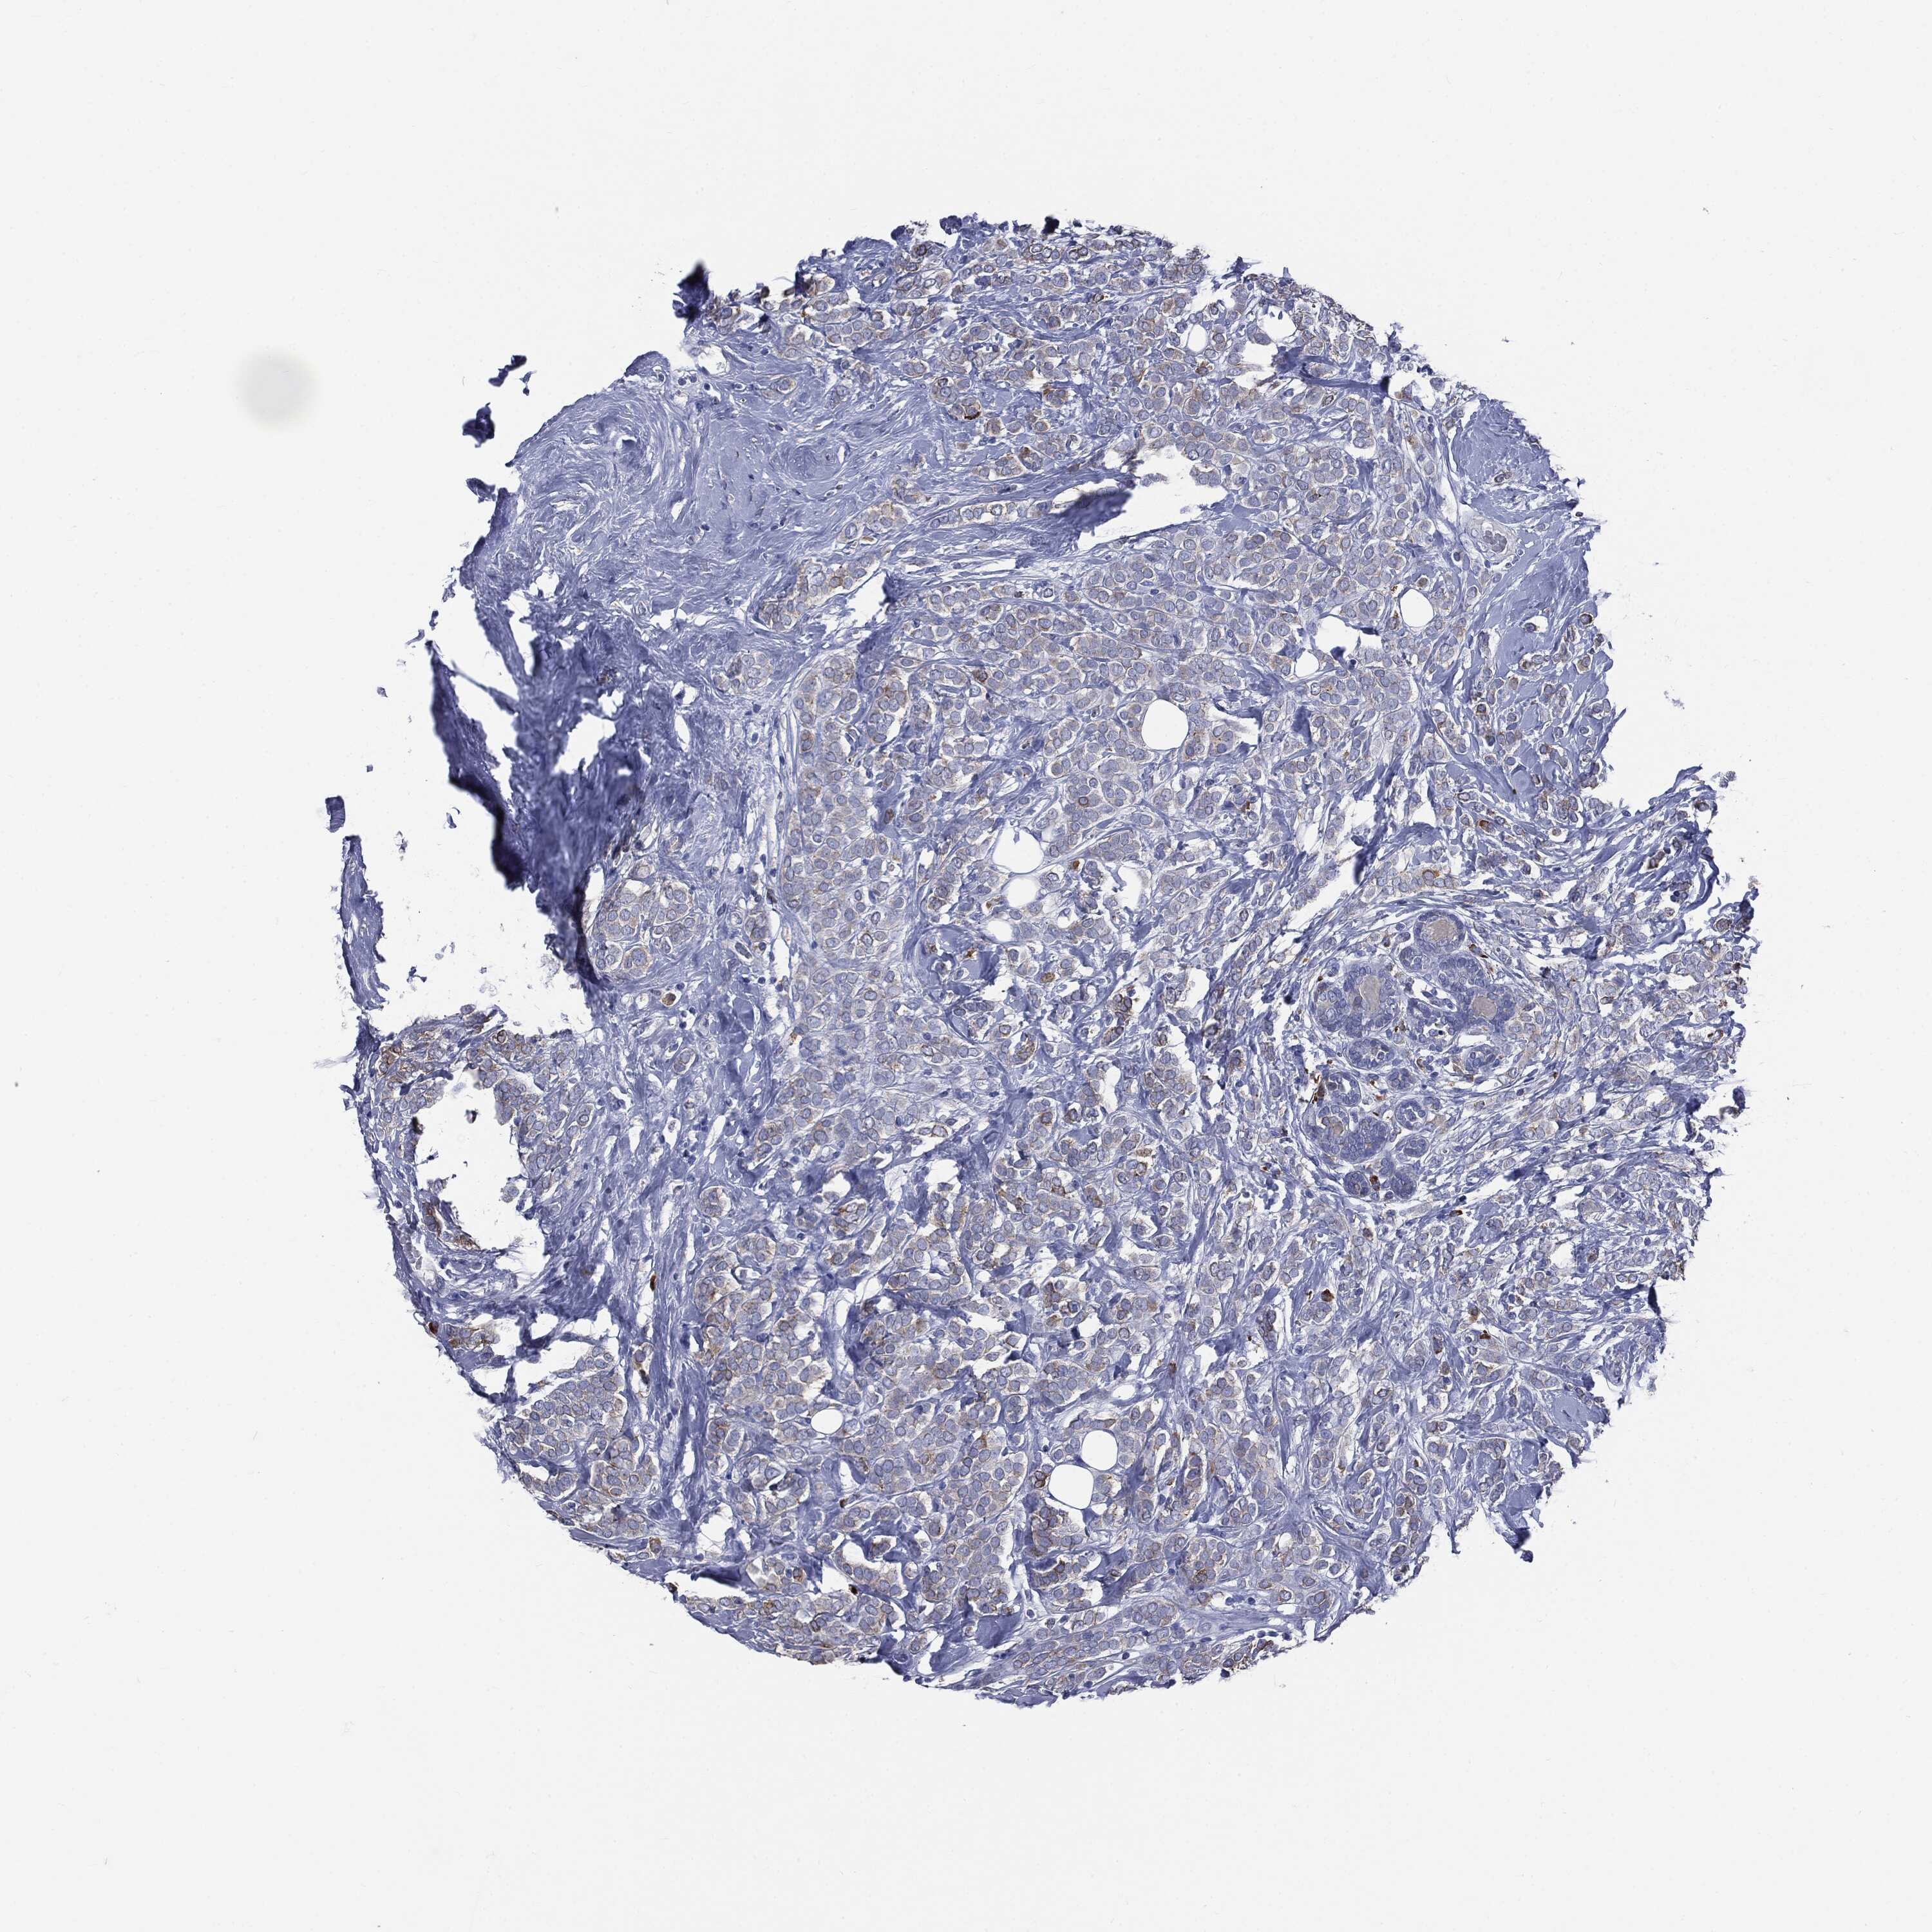

CANCER BREAST CANCER Show tissue menu

BRCA TCGA BRCA VALIDATION PROTEIN EXPRESSION

ANTIBODIES

AND

VALIDATION